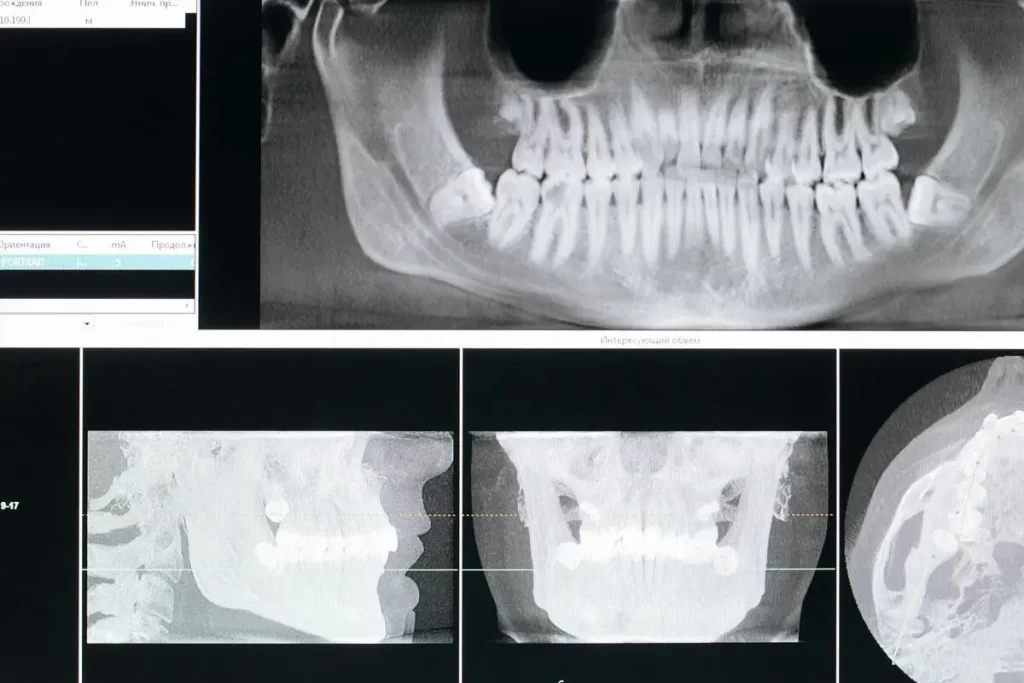

- Radiografie dentali: utili per identificare carie profonde, infezioni radicolari o danni ossei.

- Tomografia Computerizzata (TAC): impiegata nei casi più complessi per ottenere immagini dettagliate della mascella e delle strutture circostanti.